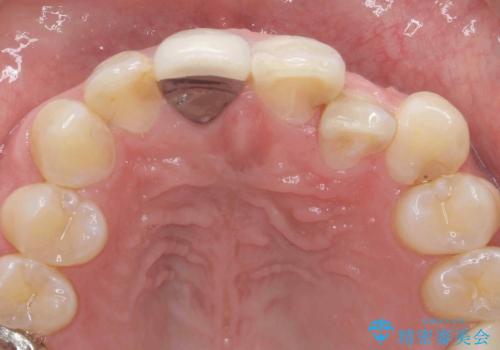

- 奥に引っ込んでいる前歯を矯正治療で並べたい!色の気になる前歯のクラウンをやり替えたい!と希望され来院されました。

奥に位置している前歯を部分ワイヤー矯正ののちマウスピース矯正インビザラインで並べ、矯正治療後に審美的なジルコニアクラウンを作製していきます。